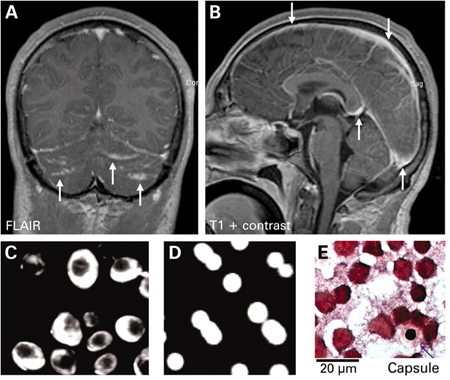

Cryptococcal meningoencephalitis. (A) Cranial magnetic resonance imaging (MRI) shows cerebellar hyperintensities (arrows) in FLAIR sequences (fluid-attenuated inversion recovery) and (B) meningeal contrast enhancement (arrows) in T1 weighted MRI. (C) Indian ink stain, (D) fungal culture, and (E) Gram stain of cerebrospinal fluid were positive

Braun J. Headache, personality changes and fine motor disturbances. BMJ Case Reports. 2009; doi:10.1136/bcr.06.2008.0093. Used with permission.